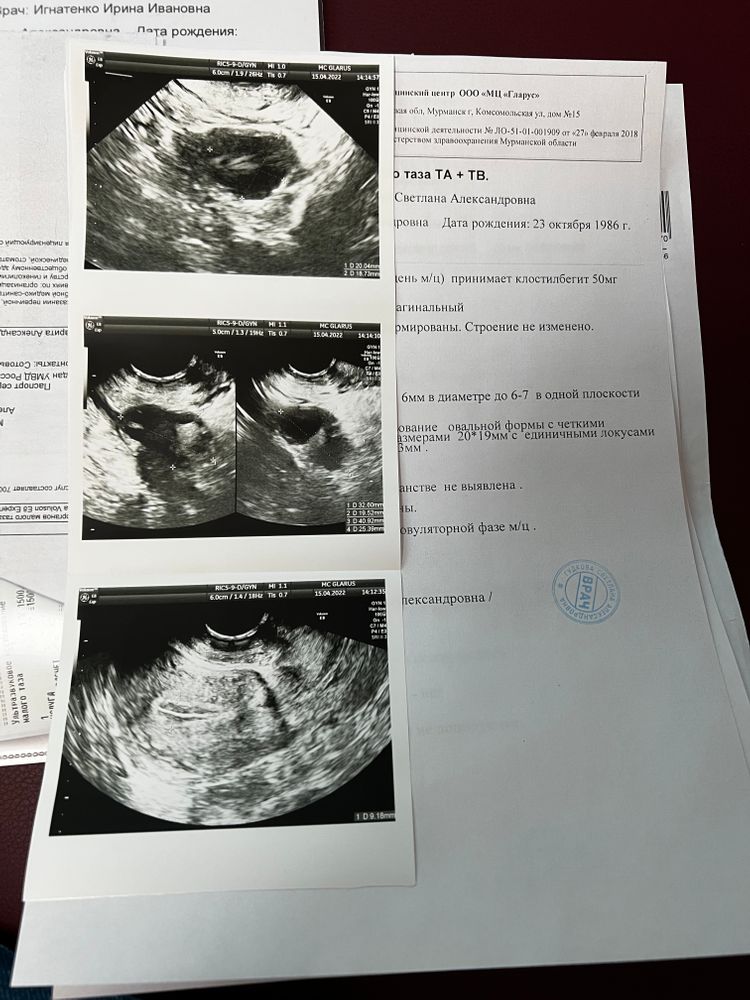

УЗИ 13 ДЦ: Доминирующий фолликул 18*16 мм, эндометрий 8 мм

УЗИ 15 ДЦ: Доминирующий фолликул 21*19 мм, эндометрий 8,9 мм. В этот день 15.04 в 17:30 сделан укол ХГЧ 6000 ед.

УЗИ 16 ДЦ: мой фолликул 25*16 мм, узист сказала, что он как будто сдувшийся, неправильный, и овуляции не будет. Врачу написала, она говорит не факт, больше ничего не сказала. Сказала сходить на узи 18.04, но я не смогу, уехала на три дня в командировку. Перелопатила весь интернет, не понимаю... Это могло быть ведь формирующееся желтое тело?

Первое фото узи на 15 ДЦ, второе на 16 ДЦ